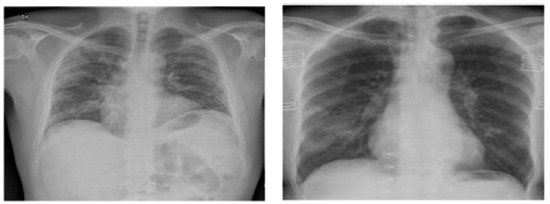

A glance at Table 1 unearths a range of classification accuracy (Acc) figures within the domain of X-ray-based COVID-19 diagnosis, spanning from 88.39% to a remarkable 98.12%. Notably, Biraja Ghoshal et al. [45] manifest the relatively modest end of this spectrum, achieving an Acc of 88.39%. Linda Wang et al. [46], in terms of classification accuracy, attain a commendable 92.4% concerning the COVIDx dataset. Meanwhile, Asmaa Abbas et al. [34] shine with an Acc of 95.12%, fortified by an impressive sensitivity of 97.91% and a specificity of 91.87%. Prabira Kumar Sethy et al. [32] also make a notable entry, securing an Acc of 95.38%. Ioannis D. Khalid EL Asnaoui et al. [47], Muhammad Farooq and Abdul Hafeez [48], and Gusztav Gaal et al. [33] bolster the upper echelons of this spectrum, boasting Acc rates of 96.23% and 97.5%, as delineated in Table 1. Furthermore, we present a compelling contrast based on the visual representations in Figure 5 and Figure 6. Our methodology emerges as a front-runner, achieving higher Acc values in comparison to the methodologies that fall within the purview of this scrutiny. Several factors underpin these remarkable findings. Firstly, manual CNN creation is a laborious and intricate endeavor, demanding a high degree of expertise from the user. The sheer diversity of potential architectural designs further compounds the intricacy, making it a formidable task even for seasoned practitioners. In this context, our investigations highlight the preeminence of evolutionary algorithms, a testament to their intrinsic capacity for optimizing accuracy throughout the search process [32]. The allure of evolutionary algorithms lies in their inherent proclivity for global exploration. This trait enables them to venture beyond local optima, delving deep into the entirety of the search space. Notably, the probability of accepting suboptimal structures through the mating selection operator adds a layer of robustness to the optimization process. As corroborated by the insights gleaned from Figure 7, our proposed approach exhibits an innate aptitude for crafting task-specific architectural designs [47]. Our method’s ability to automatically formulate CNN architectures with enhanced accuracy to those contemplated by our peers is a testament to its prowess. Crafting CNNs remains an intricate challenge, even for those with extensive domain knowledge. Notably, automated design strategies triumph over their handcrafted counterparts when dealing with radiographic images. This can be attributed to the inexhaustible permutations of potential designs, where each topology significantly influences the interactions between neural network nodes, thereby wielding a profound impact on classification performance. The paradigm of automatic architecture generation thus emerges as a promising frontier in the pursuit of higher accuracy and efficiency in the domain of medical image analysis [48].

Figure 7.

The model’s diagnostic capability to differentiate between normal and COVID-19-affected lung radiographs.

These findings further confirm our proposed algorithm’s potential to create task-dependent designs automatically when using EAs for block design. This might be explained by the fact that CNN design is very difficult, even for those with extensive experience. On radiographic images, automatic design approaches outperform manually constructed systems. The reason for this is that there is a vast variety of alternative architectures. These outcomes may be explained by the significance of network topology optimization. As each topology determines how the neural network nodes connect to each other, it has a big effect on how well the neural network can classify things. Transfer learning is then used to save time and resources by eliminating the need to train several machine learning models from the beginning in order to fulfill comparable tasks, which enables quick development and enhanced performance. Figure 8 depicts a sample of random activations in the second convolutional layer. Figure 8 illustrates the activation patterns in the second convolutional layer of our CNN model when processing chest X-ray images. The varying intensities of yellow and blue indicate the level of activation across different areas of the input feature map. High activations in yellow suggest regions where the convolutional filters are most responsive, detecting specific features or patterns relevant to the model’s task. Conversely, areas with minimal activation are shown in blue, indicating less relevance to the features the layer is designed to capture. Such visualizations provide insight into which features within the X-ray images the CNN is focusing on, potentially correlating to diagnostically significant regions for COVID-19 detection. Interpretability in deep learning, particularly in medical applications, is crucial for gaining clinicians’ trust and providing insights into the network’s decision-making process. To this end, we introduce a dedicated analysis using state-of-the-art interpretability methods to demystify our network’s behavior and provide interpretable outputs that elucidate the basis of its predictions. One of the techniques we employ is gradient-weighted class activation mapping (Grad-CAM), which generates visual explanations for decisions made by convolutional neural networks. Grad-CAM highlights the regions in the input image that are important for predictions, offering a visual understanding of which features contribute most significantly to the network’s output. By applying Grad-CAM to our network, we can visually demonstrate how the model focuses on specific areas of chest X-rays that are indicative of COVID-19, thus validating the clinical relevance of the features it learns to identify. Furthermore, we explore the use of layer-wise relevance propagation (LRP), a technique that attributes the prediction of a deep neural network to its input features, providing a pixel-level explanation of network decisions. LRP helps in identifying the radiographic features, such as ground-glass opacities or bilateral infiltrates, that the network deems critical for diagnosing COVID-19. This pixel-wise decomposition of the network’s output into inputs offers an intuitive understanding of its behavior, bridging the gap between complex model predictions and clinical interpretations. Incorporating these interpretability techniques enables us to not only bolster the credibility and acceptance of our proposed network among healthcare professionals, but also provides an invaluable tool for medical research by uncovering new radiographic features associated with COVID-19. The insights gained from these interpretability analyses contribute to a more comprehensive understanding of the network’s performance, offering explanations beyond conventional performance metrics and paving the way for a more informed and interpretable AI-driven diagnostic process.